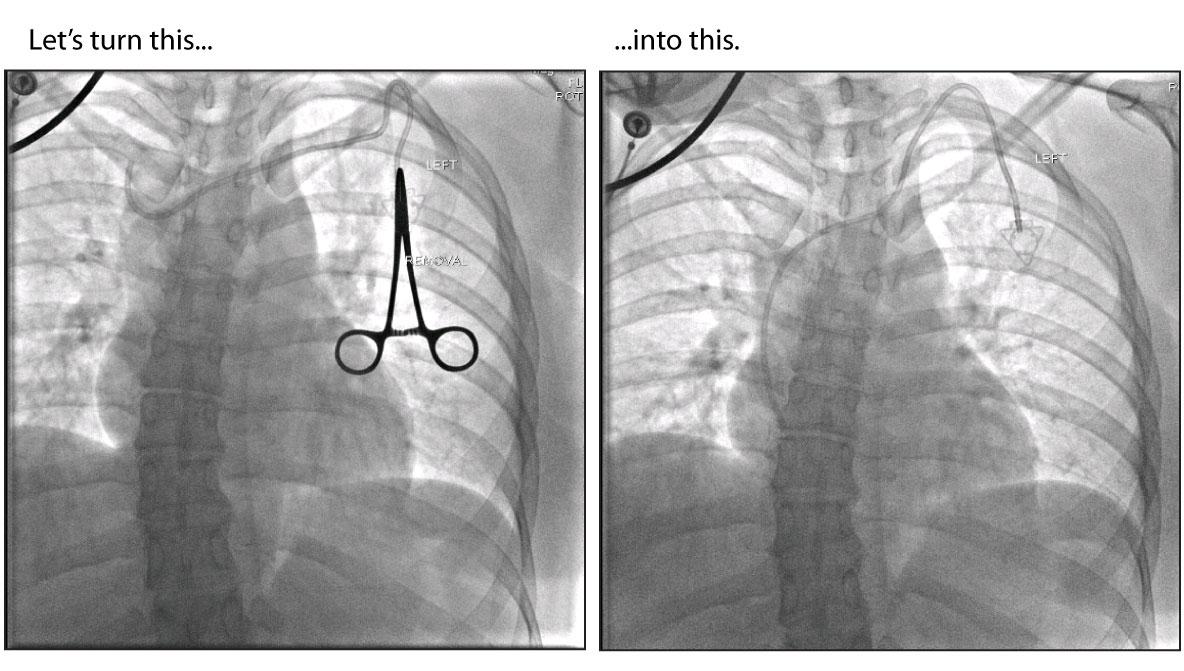

Figure - 27

Let's change this. |